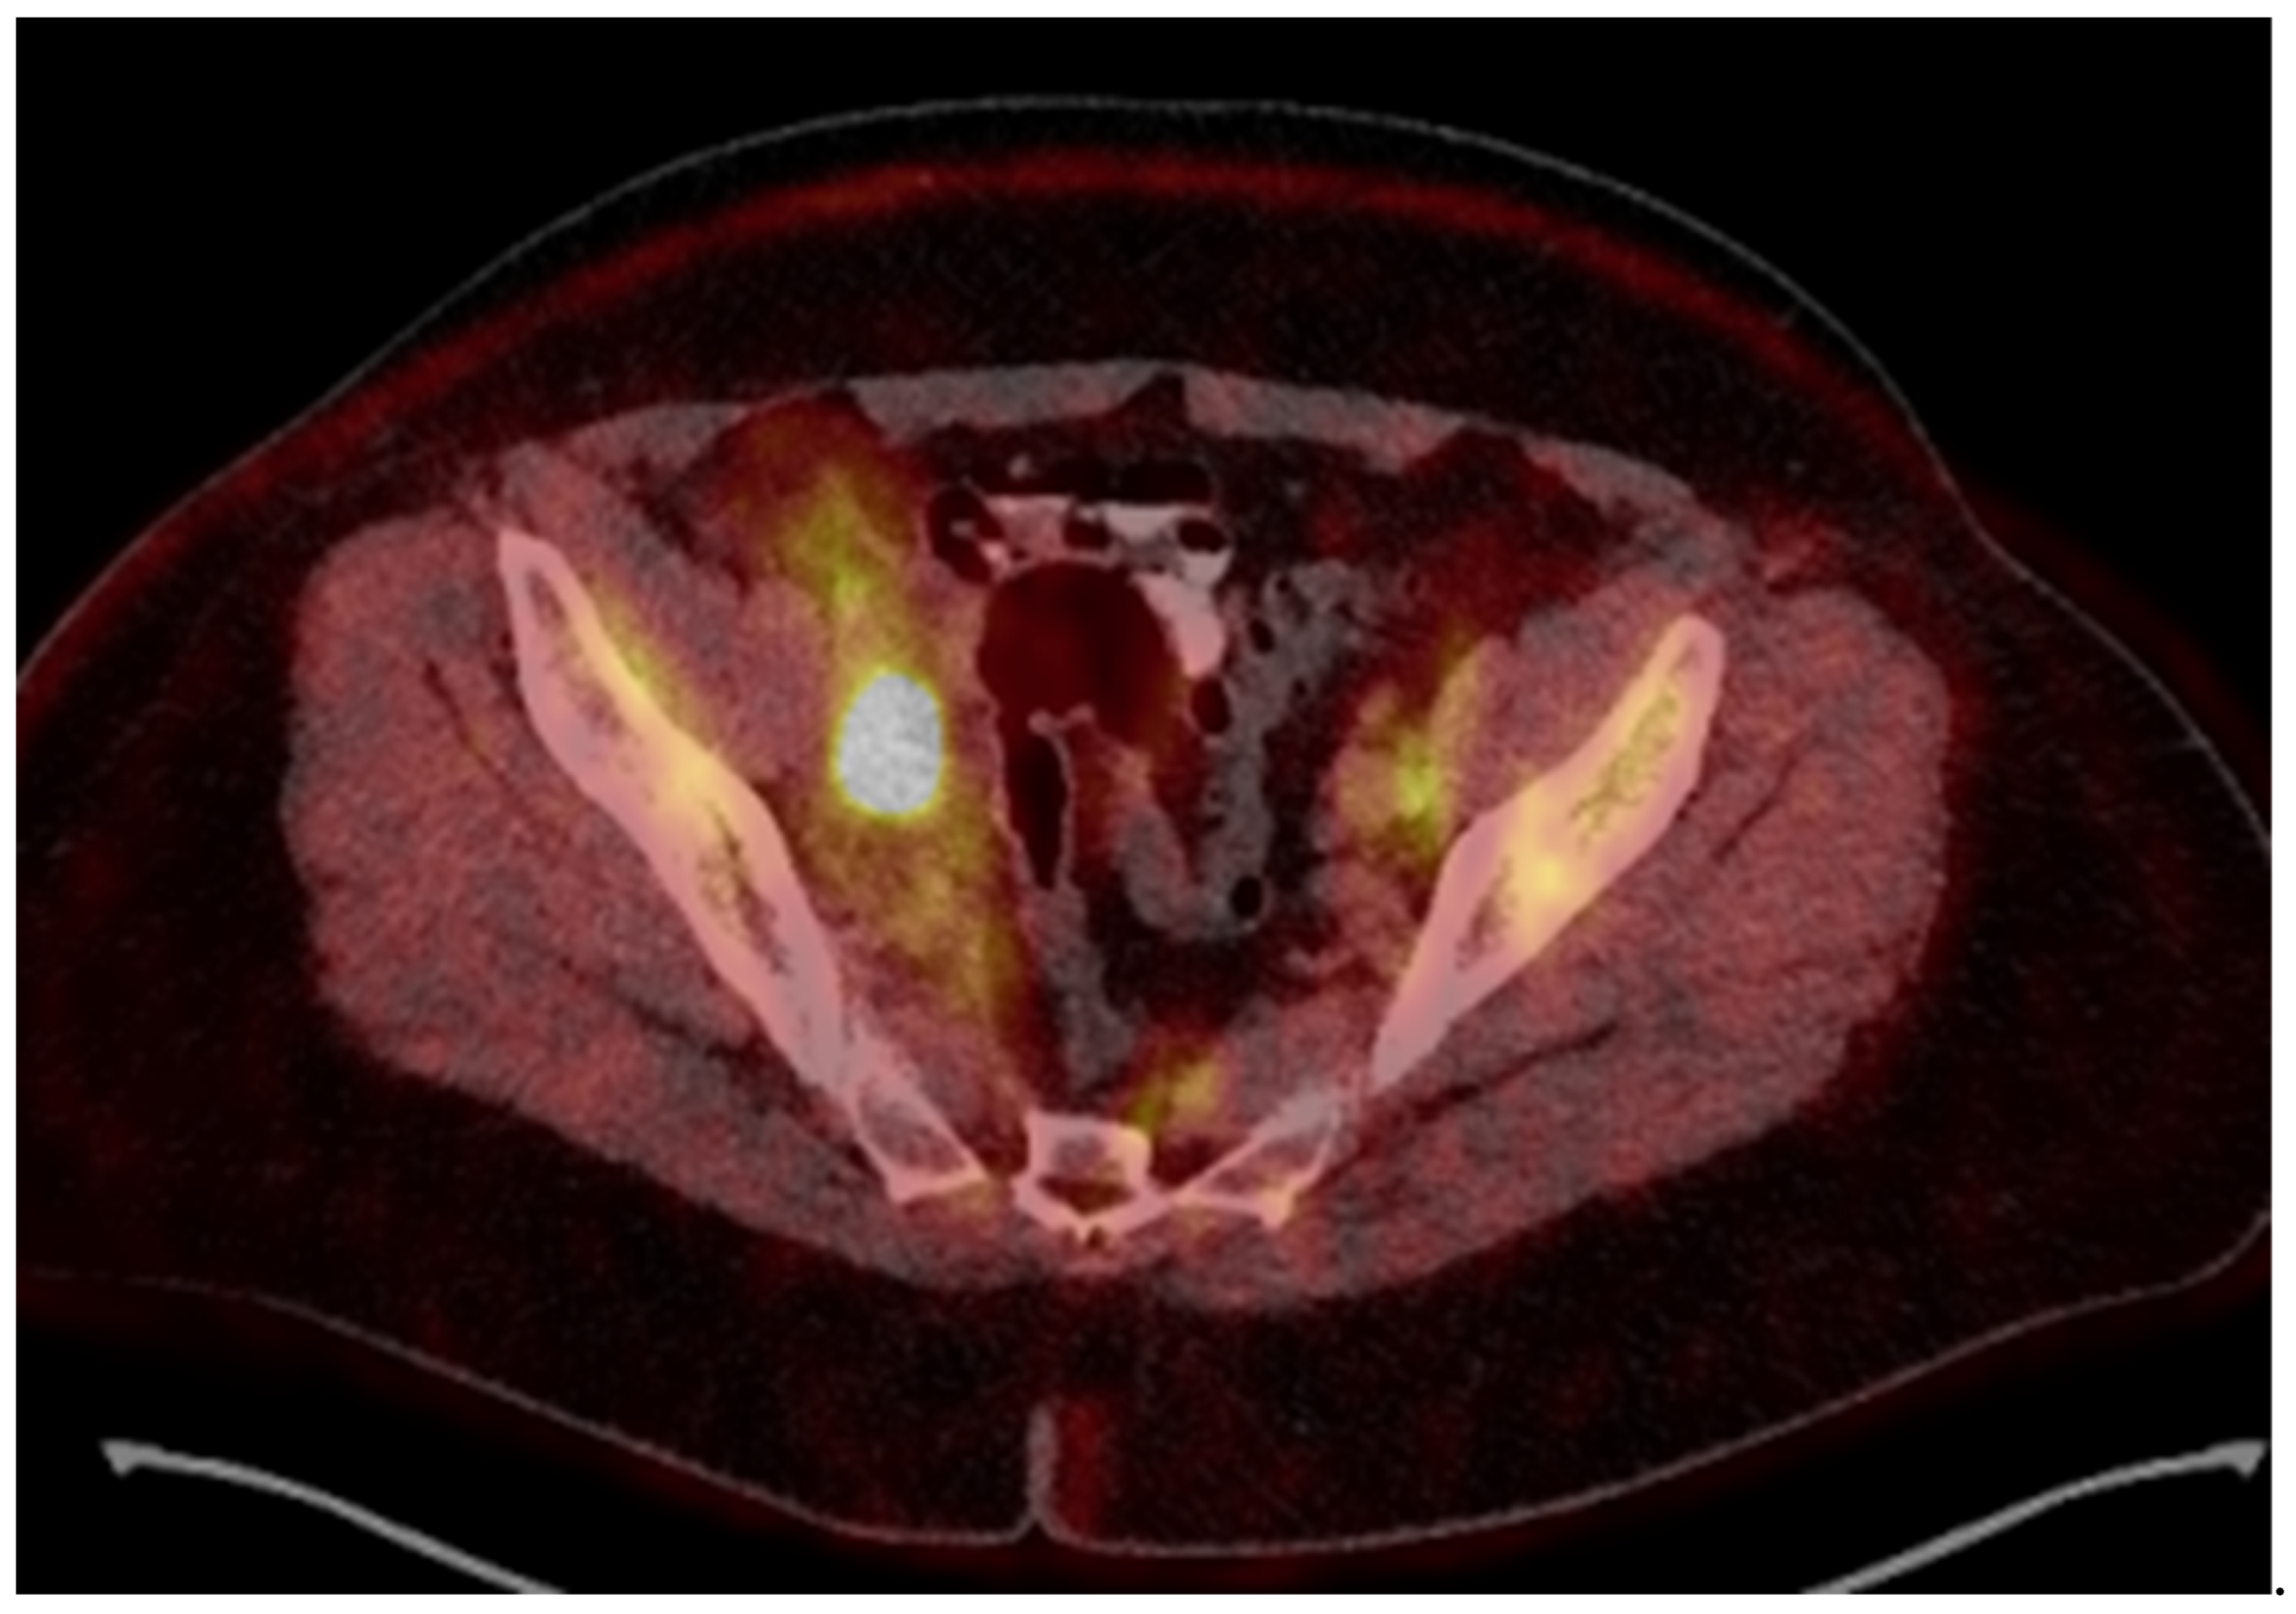

A 54-year-old woman presented in a gynecology department complaining of postmenopausal bleeding. She had been in amenorrhea for 2 years with no history of previous gynecological illness, one normal childbirth, and no family history of malignancies. She suffers from inherited recessive DEB, which was diagnosed at the age of 32. A biopsy of the uterine cervix revealed invasive squamous carcinoma G2. The patient was referred to the gynecological oncology clinic. Examination confirmed a cervical tumor with a size above 4 cm and no signs of parametrial invasion. MRT and PET/CT findings proved a tumor with an axial size of 46/32 mm and 34 mm craniocaudally with invasion of the vaginal vaults (Figure 1) and multiple bilateral pelvic lymph nodes involved, which were hypermetabolic with a highest SUV max of 42.6 (Figure 2). The stage of the disease was defined as cT2a2 cN1 M0, FIGO IIA. At the tumor board discussion, based on the current guidelines, definitive combined chemoradiotherapy was recommended. The patient presented herself at the radiation oncology department with complaints of intermittent pelvic pain, urinary stress incontinence, and occasional very mild vaginal bleeding. Dystrophic skin lesions were observed on the forearms, calves, and pubic area. Severe dystrophy of the nails was present. Recorded risk factors included obesity (body mass index 36.7) and tobacco smoking.

Figure 2.

18-Fluorodeoxyglucose (FDG) PET/CT image before treatment.